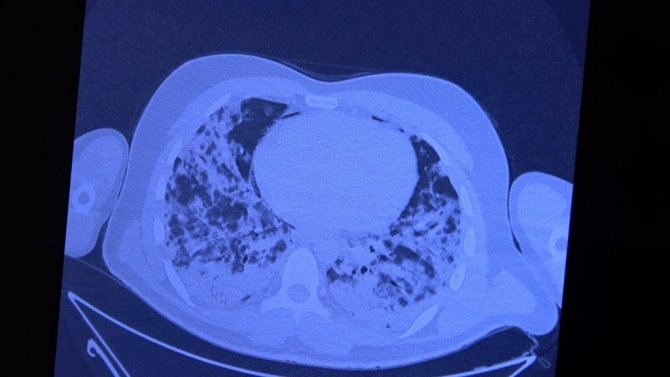

Covid-19 sürecinin başında beri 14 bin üzerinde hasta iyileştiren Prof. Dr. Şevket Özkaya, yerli aşının gelmesiyle birlikte vatandaşların aşı tereddüdünün ortadan kalkması gerektiğini kaydetti. 30'lu yaşlarda aşı olmamış 2 hastanın 10 gün içindeki akciğer tomografilerini paylaşan Prof. Dr. Özkaya, gerçeği gözler önüne serdi.

Aşı olmamış ve akciğer tutulumu yaşamış 30'lu yaşlardaki hastaların durumlarını aktaran Özkaya, "Hastalar ve hasta yakınları hep şunu merak ediyor: Hastalarının nasıl seyredeceğini soruyorlar. Ferritin, d dimer, CRP gibi parametrelerin ne olduklarını öğrendiler ve hep hastalarının kaybetmelerinin nedenlerini bu değerlerin yüksekliğine bağlıyorduk. Ama şuan şunu söyleyebilirim ki eğer Covid'e yakalanırsanız prognozunu yani hayatta kalıp kalmayacağınızın tek göstergesi aşı olup olmadığınızdır. Polikliniğe pozitif bir hasta geldiğinde aşı olmamışsa biz korkuyoruz çünkü hastayı kaybetme riski var. Bu korkuyu siz yaşamayın ve sevdiklerinize de yaşatmayın. Sizlere aşı olmamış 30'lu yaşlarda 2 tane hasta göstereceğim. Çeşitli mazeretlerle aşısını geçiştirmiş ve Covid'e yakalanmış. 30'lu yaşlarda akciğer tutulumu ile gelen genç bir hasta var. 10 gün içinde ciddi akciğer tutulumu oldu. Solunum yetmezliği gelişti ve yoğun bakımda yatırmak zorunda kaldık. Ciddi akciğer parçalanması yaşadık. Şu ana bu hasta hayatta ve kurtuldu. Bu hastanın hayatta kalması şanstı. Çok pişman oldu. "Keşke aşımı olsaydım" dedi. Aşısı yaparak taburcu ettik" şeklinde konuştu.